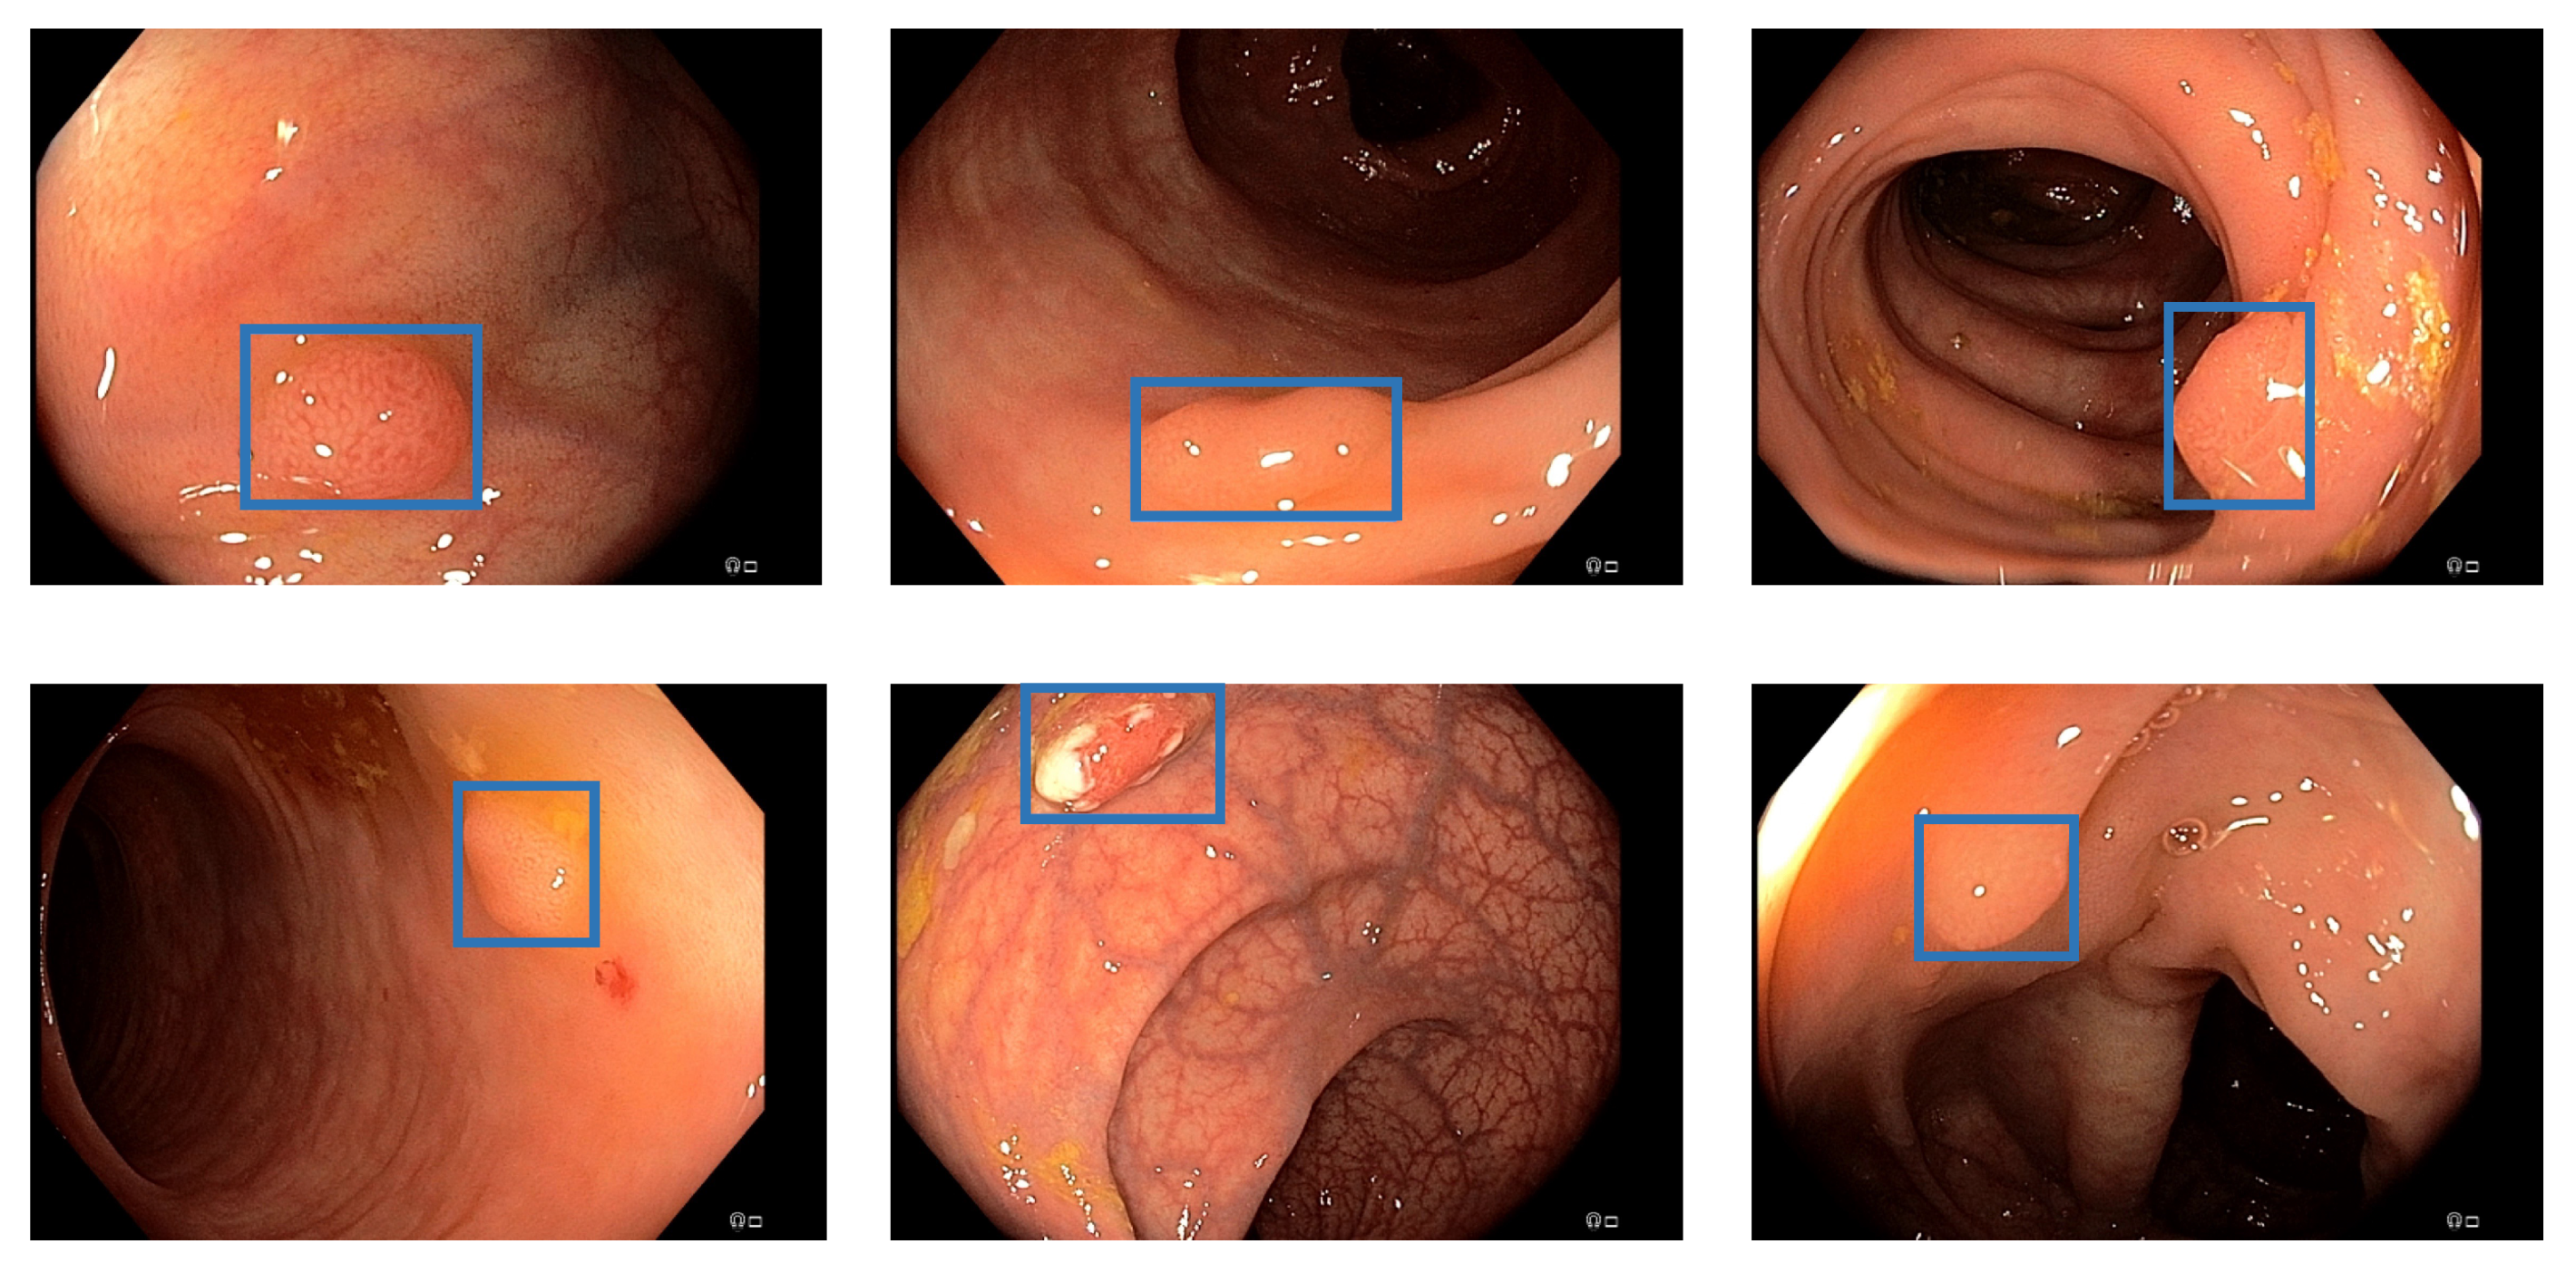

3.2. EndoData Evaluation

Our own validation set (EndoData) allows us to detect polyps more precisely and accurately. Table 8 shows an overview of the videos in the dataset and Figure 13 shows examples of the dataset. The EndoData dataset records sequences as the polyp appears in the scene. Therefore, polyps are marked precisely with their first appearance. In comparison, the polyp sequence of the CVC-VideoClinicDB dataset might not start when the polyp is already detected. Those early seconds are crucial as the gastroenterologist has to identify and not miss the polyp during this time. If the polyp is not detected in the early sequence, it increases the risk of missing it. As we like to focus on this early detection, we introduce a second metric that can just be evaluated with a dataset like ours. This metric marks the seconds from first seeing the polyp to first detecting the polyp. We call it first detection time (FDT). Additionally, we compute the FPs and the false positive rate (FPR) per video (Table 10 and Table 11).

The evaluation for FDT is shown in Table 10. For the YOLOv5 (base), only video 4 does not receive a delay in detection. Nevertheless, all polyps are detected at least once with every algorithm. The FDT of YOLOv5 (base) is inferior in all videos to the other models. The Faster R-CNN algorithm does recognize the polyp in the first frame in videos 1, 3, 4, and 10 for YOLOv5 (adv.), REPP, and RT-REPP. The FDT for these three models does not differ except for video 7. This difference is due to REPP and RT-REPP removing the detection in the post-processing process. Those three approaches also detect the polyps in the first frame for videos 1, 3, 4, and 10, like Faster R-CNN. For 9 out of the 10 videos, FDT is under 1 s; therefore, the polyp should be sufficiently detected to show the gastroenterologist its position. Nevertheless, in video 7 there is a FDT of 2.6 s. Such a late detection of a polyp may miss the polyp for the gastroenterologist. However, REPP and RT-REPP are reducing the number of FPs from an average of 113.5 to 78.3 and 91.3.

We evaluate the models on our dataset with the same metrics as the CVC-VideoClinicDB dataset. On the EndoData dataset, the results are equivalent to the predictions of the CVC-VideoClinicDB data. The mAP is, on average, consistently lower than the F1-score. Additionally, REPP is again the best scoring model. Again most values are over 90% F1 value for RT-REPP. The dataset appears to be more challenging than the CVC-VideoClinicDB dataset as there are just five videos with F1-scores over 90%.